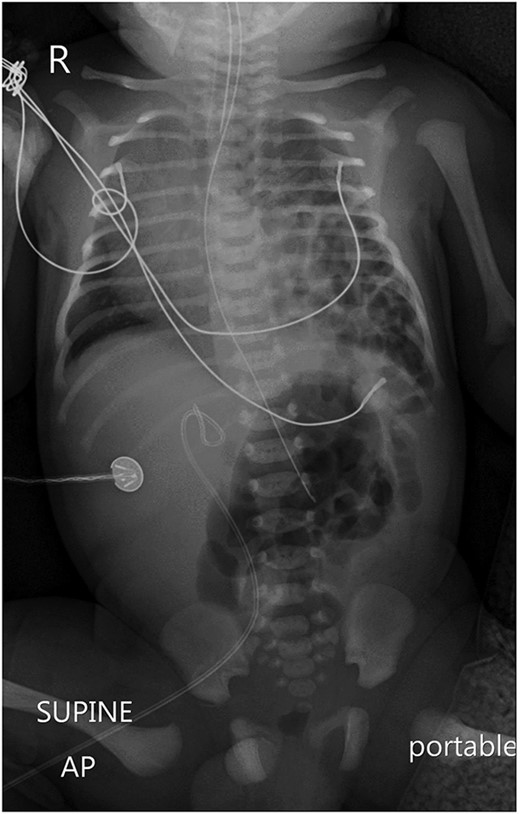

Postoperatively, a chest X-ray revealed a small left-sided pneumothorax that resolved in a few days (Fig. 2). Three days after the surgery, the fentanyl infusion was stopped, and the patient was extubated to a high-flow nasal cannula for 5 days. On the same day, the patient was noted to have a greenish-yellow aspirate. The patient was febrile the day after, a septic screen was done, and the patient was treated with ceftriaxone and vancomycin for 2 weeks. Furthermore, the surgical site was noted to have purulent discharge, for which fusidic acid was locally applied for 2 weeks. Abdominal ultrasound conducted a week after surgery showed an oval collection of fluid with intrinsic echoes, possibly a splenic hematoma, in the left upper quadrant, which was self-limited after 2 months of follow-up (Fig. 3). Before discharge, the patient’s parents were advised on a nursing plan, oral sucrose for analgesia and ranitidine.

A portable X-ray photo of the chest, abdomen and pelvis taken postoperatively shows the expansion of both lungs and midline mediastinal position. A small subpulmonic pneumothorax on the left side is visible, for which a chest tube was inserted.